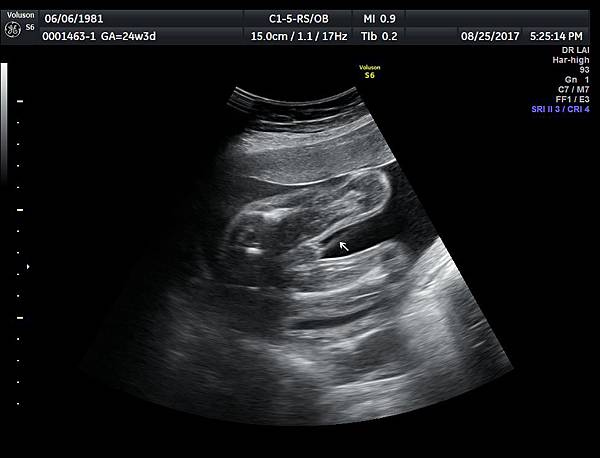

今天下午一位28歲第一胎的孕婦來診所做超音波檢查,之前他們一直認為懷的是女兒(檢查前資料顯示胎兒是女生);今天我的診斷胎兒是男生,但是懷疑有尿道下裂的問題(附圖 1~4),我的建議是抽羊水做染色體基因檢查,除了確定性別之外,也可以排除是否合併基因異常。

2018年3月的一位孕婦,產檢期間醫師也覺得比較像女生,羊水報告卻是男生,經過我的檢查,診斷是胎兒懷疑有尿道下裂(附圖 5.),產後證實是尿道下裂(附圖 6.7.)。

診斷尿道下裂常用的鬱金香sign(tulip sign)(附圖 10.11.),它的特徵就是龜頭陷入陰囊中間,胎兒如果是男生,一定要看到龜頭離開陰囊,這樣就沒有問題,每次遇到尿道下裂的個案時,我都會有一個感觸,男生如果能站著尿尿都要很感恩。